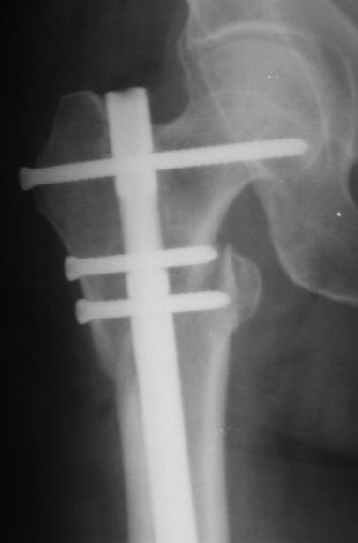

В частности, его возможности при фиксации переломов проксимального отдела бедра - в сравнении с другими, имеюшими лишь по одному статическому и динамическому отверстию и с кондуктором для введения 2 винтов.

Это было года 2,5 назад, мы тогда еще уточняли возможности шинирования с угловой стабильностью гвоздем с поперечным расположением винтов при переломах проксимального отдела бедра. Пациенту не пришлось приобретать намного более дорогой рекон или проксимальный гвоздь. В приложении еще несколько примеров применения того гвоздя при высоких переломах бедра, в том числе с более латеральной точкой входа. Гвоздь изгибаем для этого.